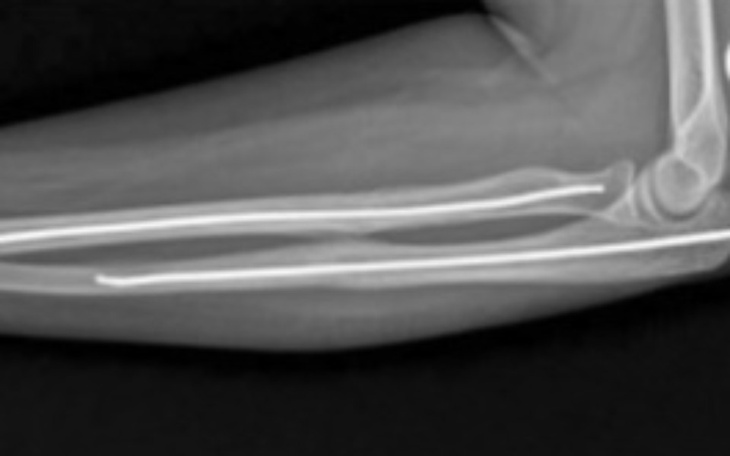

Witam jestem tatą Damiana miał straszny wypadek i złamał tak jak na zdjęciu potrzebujemy pieniążków proszę wpłać nawet złotówke